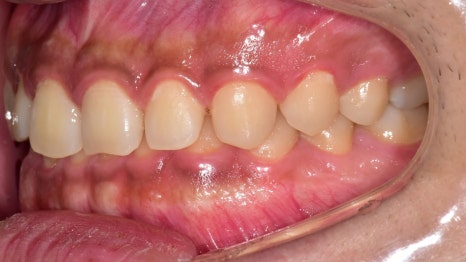

이제 아랫니가 많이 보입니다.

올바른 피개량을 갖게 되어

이전에 비해 훨씬 편안하고

안정적인 모습으로 바뀌었습니다.

절단연부터 느껴지는 비대칭도

상당 부분 나아진 것을 볼 수 있으며

정중선도 알맞게 일치하고 있네요.

구치부 교합도 훨씬 긴밀해졌으며

톱니바퀴와 같이 잘 물리고 있는 모습입니다.

전체적으로 정상 교합으로 바뀌었는데요.

교합면에서 관찰해보면

밖으로 뻗쳐 있던 어금니들도

제 위치를 찾아 돌아온 것을 볼 수 있네요.